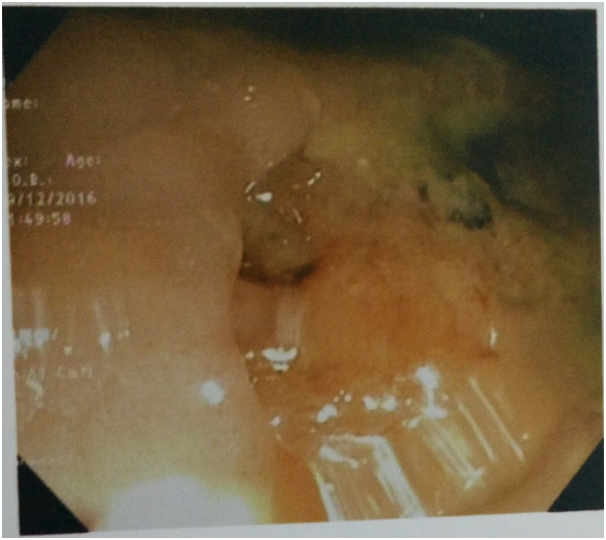

The investigations showed Hb-12.1gm/dl, ESR-45mm 1st hour, total leucocyte count-8700/mm3, differential leukocyte count: neutrophil(63%), lymphocytes(27%), eosinophils(5%), monocytes(4%), and basophils(1%). Biochemical investigations showed Fasting blood glucose-98.0mg/dl, blood urea-30.8mg/dl, serum creatinine-1.1mg/dl, serum bilirubin-0.8mg/dl, AST-34.0 IU/L, ALT-32.3IU/L, Alkaline phosphatase-100.8IU/L. Viral markers for HIV, HBSAg, and HCV was found to be negative. Radiography of Chest showed left sided pleural effusion. Radiography of thoracolumbar spine did not show any abnormality. Fistulo gram delineated the tract which was directed upwards posteromedialy. Fine needle aspiration cytology (FNAC) of right inguinal lymph node showed granular necrotic material with few lymphocytes highly suspicious of tuberculosis. MRI of thoracic spine (T2WI) showed a nodular hyperintense intramedullary lesion at T4 vertebral segment with surrounding hyperintense edema extending from T2to T6 vertebral level (Figure 1). With T1 contrast isointense lesion at D4 vertebral segment showed thick ring enhancement. Colonoscopy also showed a large ulcer in the lower part of rectum suggestive of Tuberculosis (Figure 2). The histology of biopsy material taken from perianal lesion showed caseating necrosis, epithelioid cells with Langhan’s type multinucleated giant cells suggestive of Tuberculosis (Figure 3).

Figure 3 Biopsy showing caseous necrosis, epitheloid granuloma and Langhan’s type multinucleated giant cells.